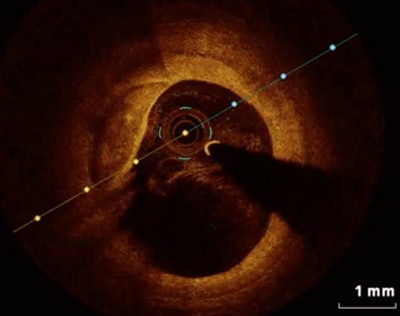

The study surveyed the prevalence and clinical predictors of coronary plaque rupture in more than 150 patients with coronary artery disease. It examined so-called "culprit lesions" in patients who had coronary plaque rupture or thin-cap fibroatheroma at optical coherence tomography (OCT) after coronary CT angiography.

OCT has emerged in recent years as the most accurate modality for intracoronary evaluation, the authors wrote. It does an excellent job in characterization of plaque and is more accurate than intravascular ultrasound.

As an imaging modality, OCT is feasible and safe, showing all of the various microstructures of atherosclerotic plaque, they wrote. But why some plaque ruptures lead to a specific acute coronary syndrome such as STEMI or NSTEMI remains unclear, the study team added.